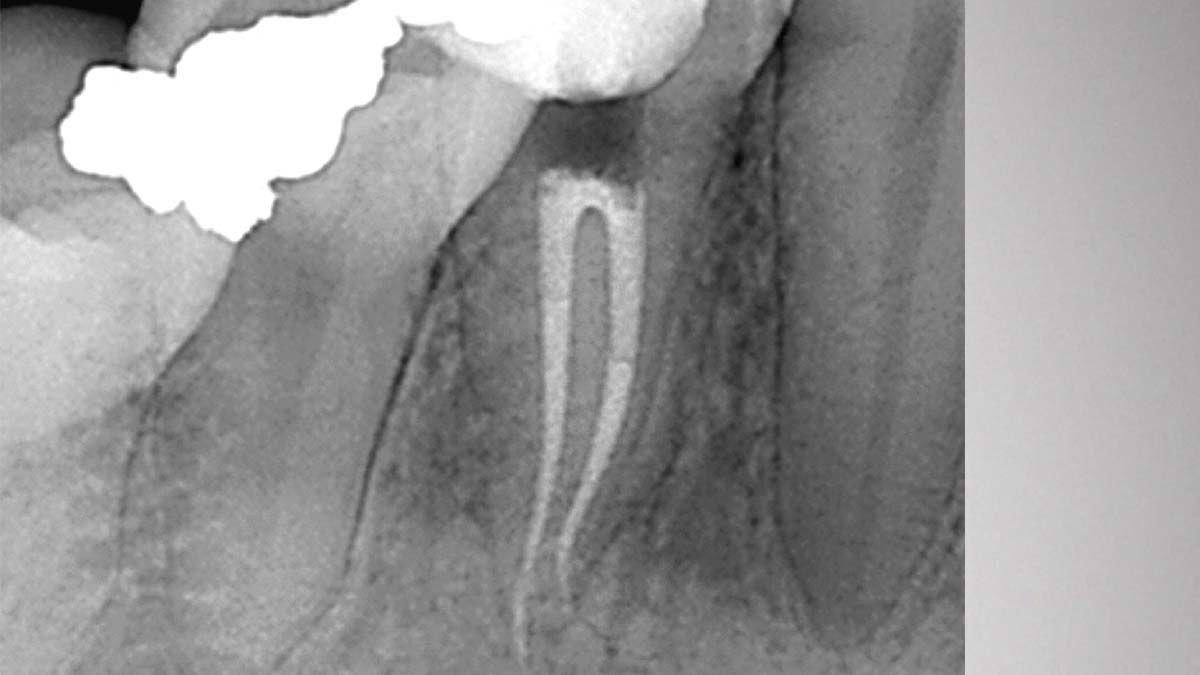

On the left: Using different formulations of gutta-percha in one case can cause varying degrees of opacity.

Image courtesy of Dr. Phillip Bell, Mooresville, NC

On the right: Gutta-Smart and Conform Fit feature the same advanced gutta-percha for radiographic consistency.

Image courtesy of Dr. Nathaniel Behrents, Fayetteville, AR